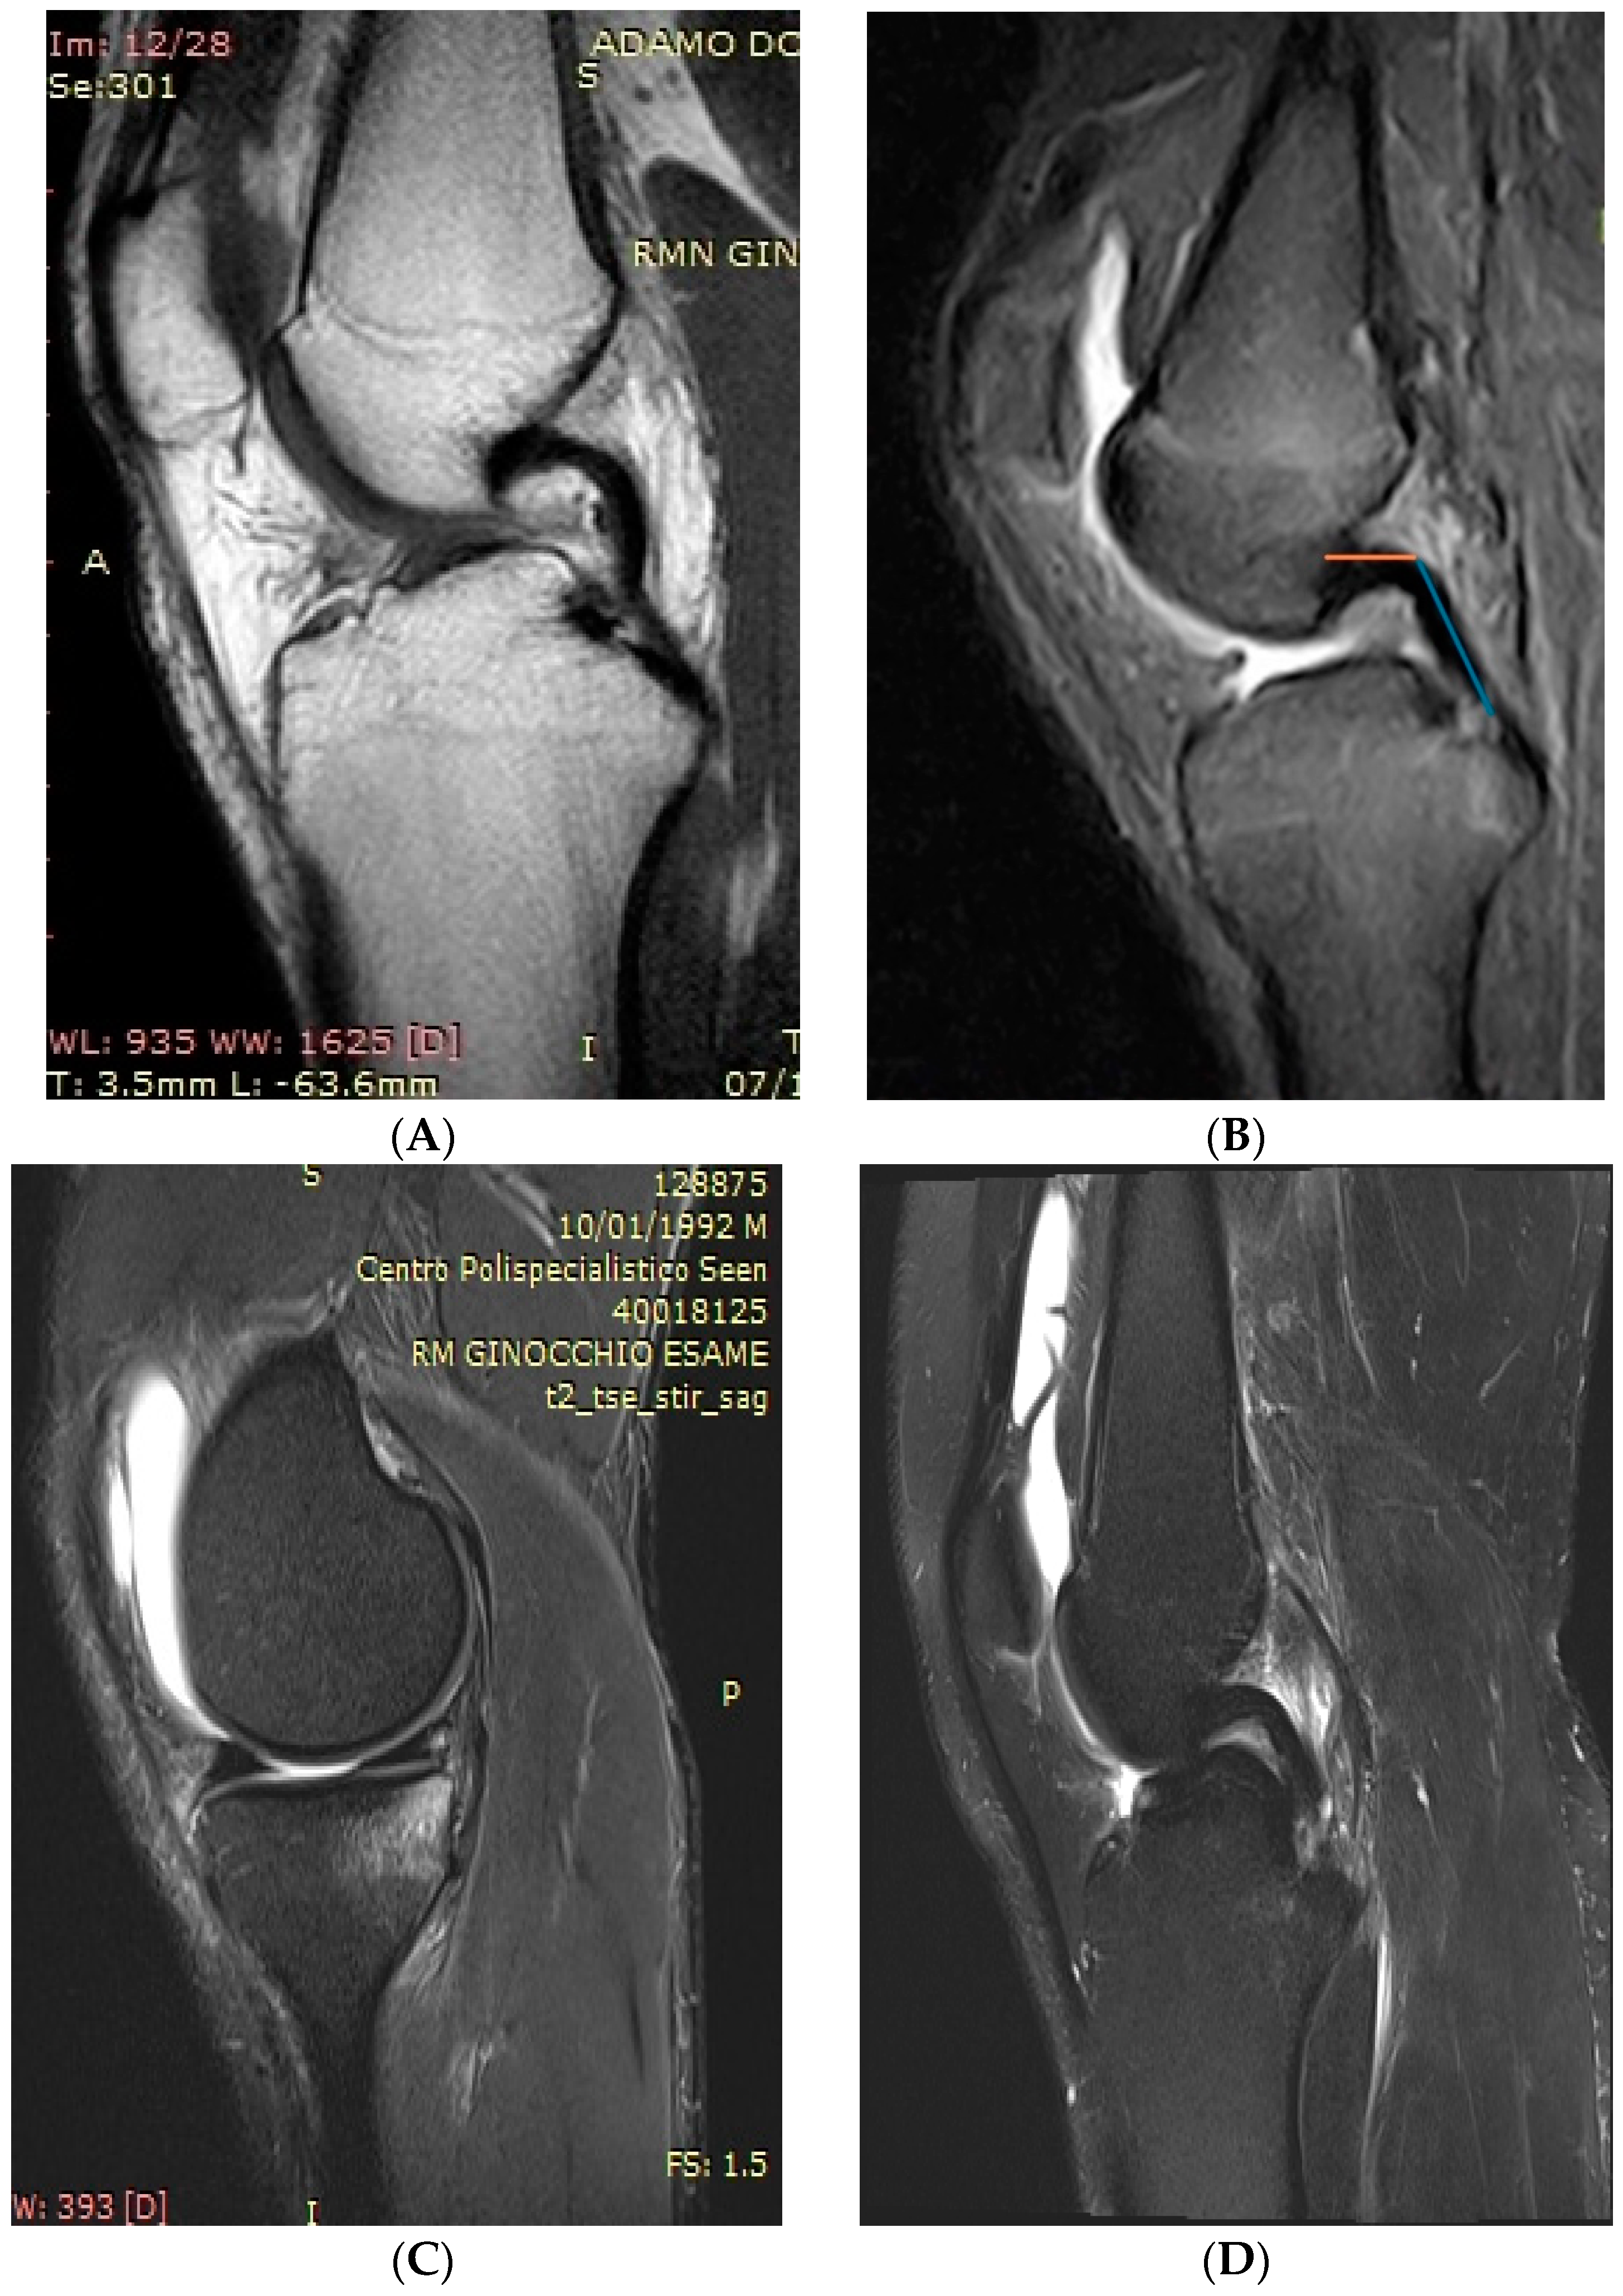

On the sagittal view of the MRI, the angle formed between the proximal and distal parts of the PCL was measured, evaluating the same sagittal cut according to the method described by Yoon et al. [9]. The angle is formed by the intersection of two lines, which follow the proximal and distal parts of the PCL (Figure 2).

Figure 2. (A,B) PCL buckling is visible on sagittal views focusing on the center of the intercondylar notch. PCL buckling angle was calculated according to the method described by Yoon et al. [9]. It is formed by the intersection of two lines which follow the proximal and distal portions of the PCL (C,D) MRI sagittal images of ramp and bucket handle lesions.